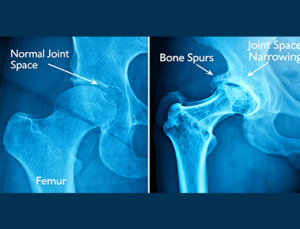

Osteoarthritis, the most common type of arthritis, is the breakdown of cartilage that keeps bones from rubbing together. It most commonly occurs in the weight-bearing joints, such as the hips and knees, and can be made worse by other factors like overweight.

As the cartilage wears away, the bone underlying it degenerates, and other parts of the joint, such as ligaments and muscles, become altered as well. Usually appearing at middle age and developing slowly, osteoarthritis is characterized by pain that gets worse as the day goes on, stiffness and decreased motion, swelling in the joint, sounds (like clicking or crunching noises) when moving the affected joint and visible deformity of the joint.